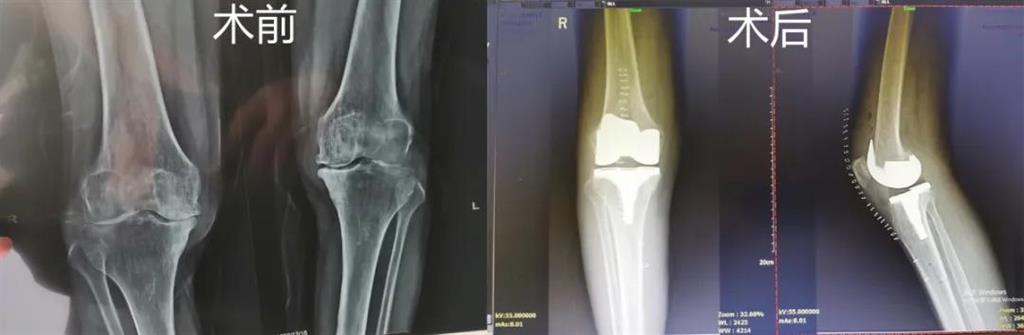

和平國際醫(yī)院副院長、骨科中心主任劉丹在診斷后發(fā)現(xiàn),老人雙側膝關節(jié)患有骨性關節(jié)炎,右側膝關節(jié)較為嚴重,而且關節(jié)磨損嚴重關節(jié)間隙基本消失

經過進一步檢查后,劉丹帶領團隊在計算機導航系統(tǒng)的輔助下,為老人實施了右側全膝關節(jié)置換手術。術中出血明顯減少,術后疼痛腫脹等反應輕微畸形矯正力線恢復理想,而且功能恢復快速,術后四天就可以下地行走。